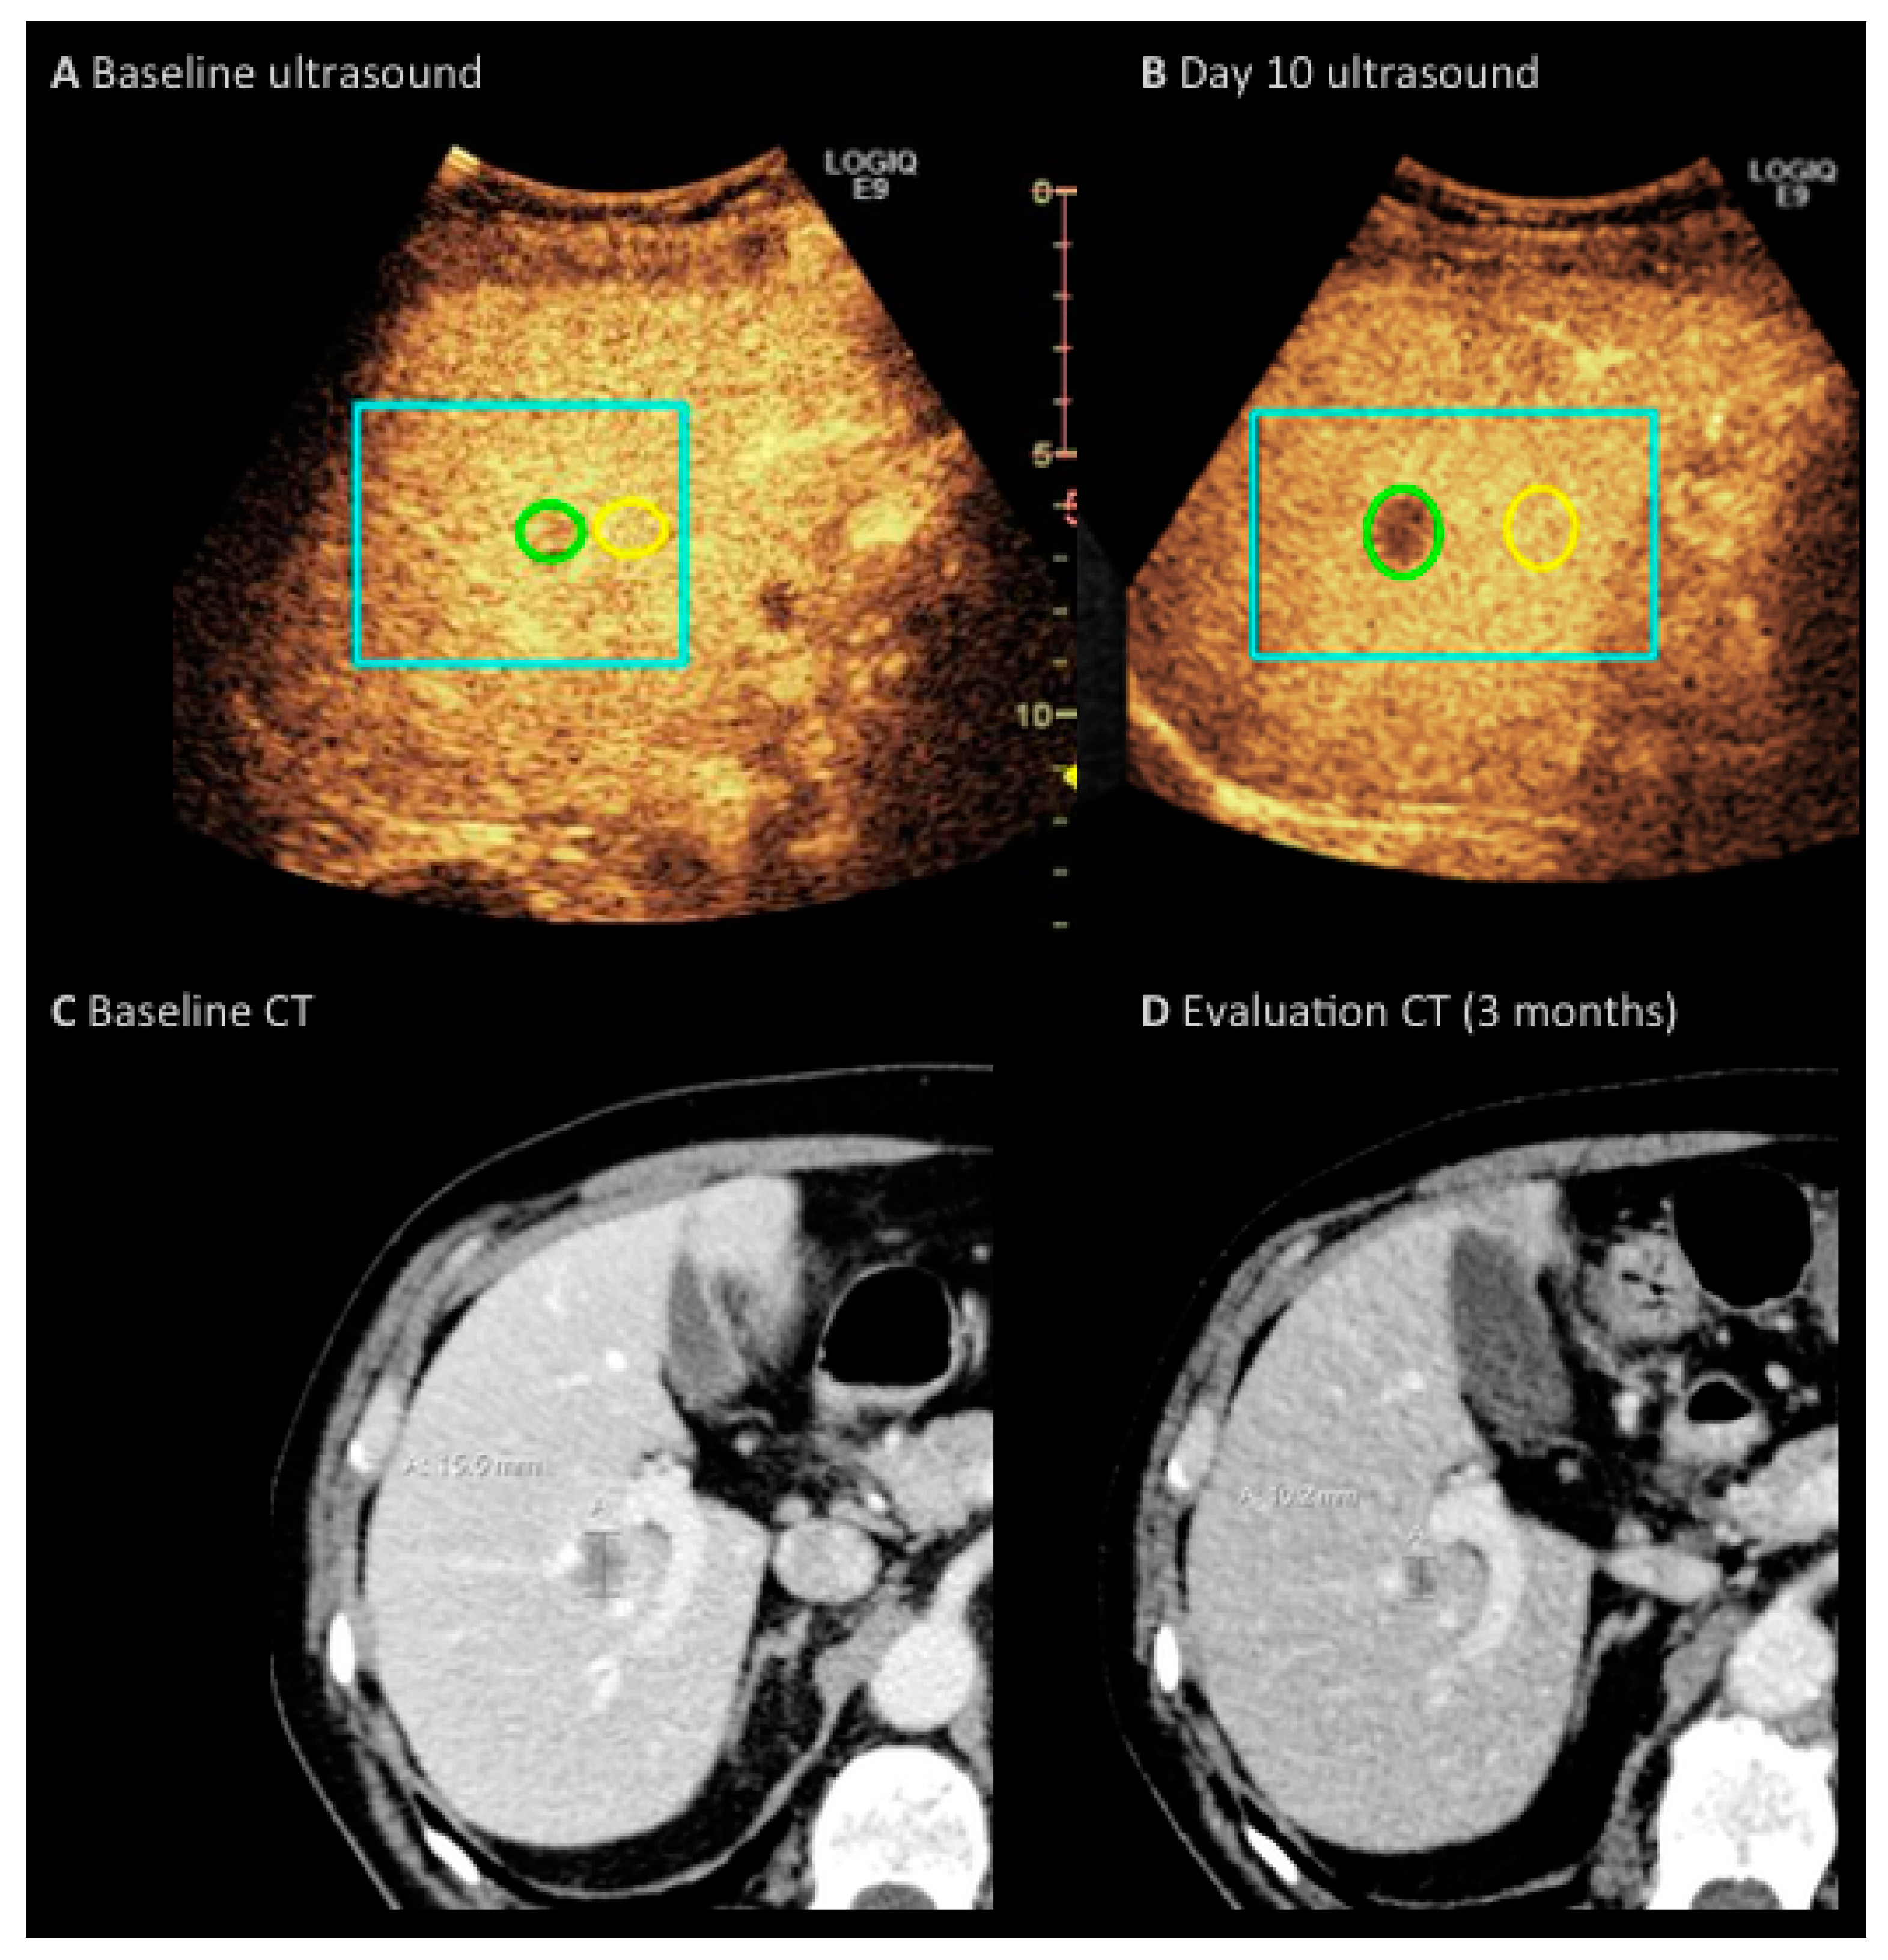

2.2. Imaging Protocol

2.3. Imaging Analysis